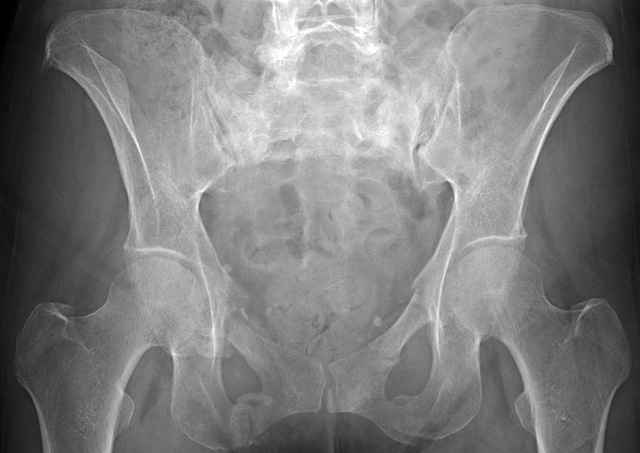

Here are a recent patient’s example slides...